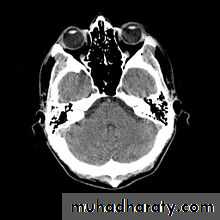

FixedWhen reviewing an MR image, the easiest way to determine which pulse sequence was used, or the "weighting" of the image, is to look at the cerebrospinal fluid (CSF). If the CSF is bright (high signal), then it must be a T2-weighted imaged. If the CSF is dark, it is a T1-weighted image.